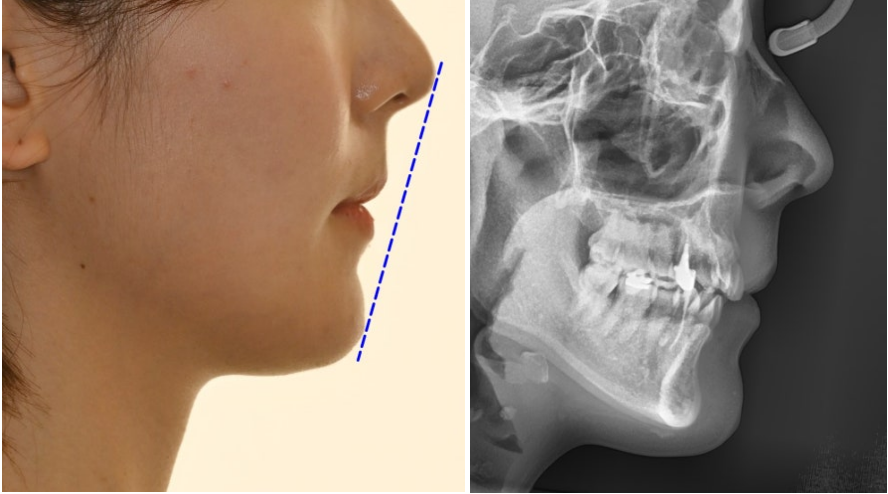

| 2. 정밀한 초진 검사가 성공의 첫걸음

23.10.20

먼저 구강 내 전체 상황을

파악하는 것부터 시작합니다.

위 사진을 보면

전체적으로 치열이 틀어져 있는 것을

확인할 수 잇었으며

결손된 부위로 인해

아랫니가 벌어져 있는 것을

확인할 수 있습니다.

양쪽 교합을 확인해 보면

왼쪽 어금니 부위가

반대교합이 확인됩니다.

윗니는 삐뚤빼뚤하며

위 앞니가 아랫니를 덮는 양이 부족합니다.

교합면을 보았을 땐

아래 앞니 2개가 결손되어 있으며

사이 공간이 있습니다.

위아래 앞니 사이 거리가 과도합니다.

얼굴 분석을 통해서는

전체적인 얼굴 형태의 변화를 관찰합니다.

턱끝이 뒤로 들어가 있는 무턱 형태인지,

코와 입술, 턱끝의 상대적 위치 관계가

어떻게 변화했는지를

세밀하게 평가하는데요.

입술의 지지가 부족하여

함몰되어 보이는 정도도

같이 확인하게 됩니다.